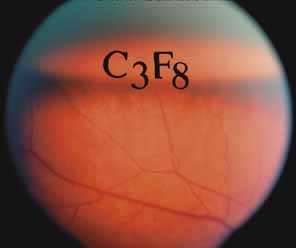

Intravitreal gas has become a standard part of complex and routine retinal repairs. The appropriate use of intraocular long-acting gas tamponades requires a thorough knowledge of the time-expansion characteristics of the chosen gas (sulfur hexafluoride; perfluoropropane) as well as the clinical situation (partial or total fill of the vitreous cavity).47 Sulfur hexafluoride has a peak expansion 6 to 12 hours after injection. A 20% mixture usually represents the concentration that will not expand in volume when a total fill of the vitreous cavity is performed. Perfluoropropane expands acutely over a similar time frame. A 14% mixture with room air represents the “safe” nonexpansile percentage when the total volume is replaced (Fig. 8).